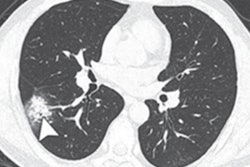

In their study, Lan's team included four patients, all of whom were medical personnel (one hospitalized, three quarantined at home) treated at Zhongnan Hospital between January 1 and February 15. All had positive RT-PCR test results and ground-glass opacification or mixed ground-glass opacification and consolidation on CT; disease severity was mild to moderate.

After hospital discharge or the end of quarantine, the patients underwent RT-PCR tests five to 13 days later. All were positive. The patients then had three more RT-PCR tests over the next four to five days, and all tested positive, although they were asymptomatic by physician examination and chest CT. None of the patients reported contact with anyone with respiratory symptoms, and none of their family members were infected.